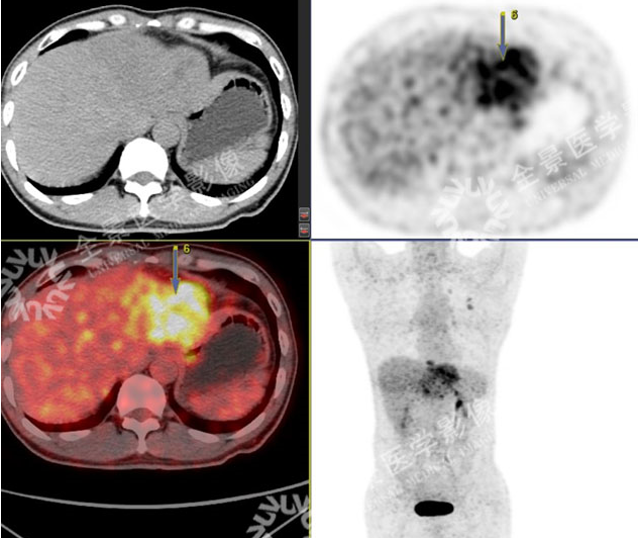

男 50岁 小肝癌:

案例一